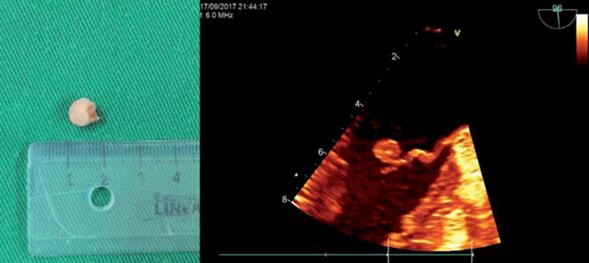

Se realiza cirugía cardíaca. Se extirpa masa redondeada y pediculada de 7 mm de longitud adherida a la valva anterior mitral (Figura 1).

Figura 1: A izquierda: pieza quirúrgica extirpada de 7 mm de longitud, con pequeño pedículo. A derecha: ecocardiograma transesofágico, se observa masa redondeada adherida a la superficie auricular de la valva anterior mitral. Nótese la presencia de microcalcificación central y ecogenicidad inhomogénea.